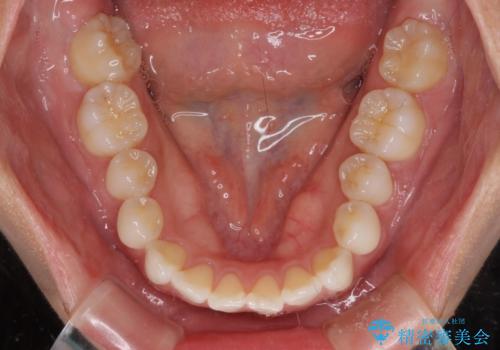

- 前に出ている上顎前歯が気になるとのことで来院された患者様です。

インビザラインを用い、IPR(歯と歯の間を削る)と歯列全体を後方に移動させることで、可能な限り前歯の突出感を改善することとしました。

元々の歯列も整っており、横顔の印象の出っ歯ではなかったため、仕上がりに満足できない可能性があると心配しておりましたが、口が閉じやすくなり、患者様には大変満足していただきました。